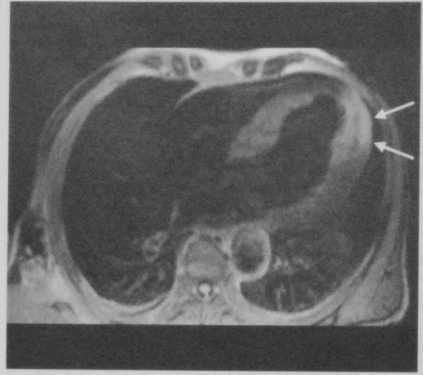

Переднебоковой ИМ у мужчины 68 лет. На Т2-взве- шенной МРТ в режиме TSE (четырехкамерная проекция) с темной кровью определяется гиперинтенсивность сигнала от зоны инфаркта (стрелка) из-за отека миокарда.